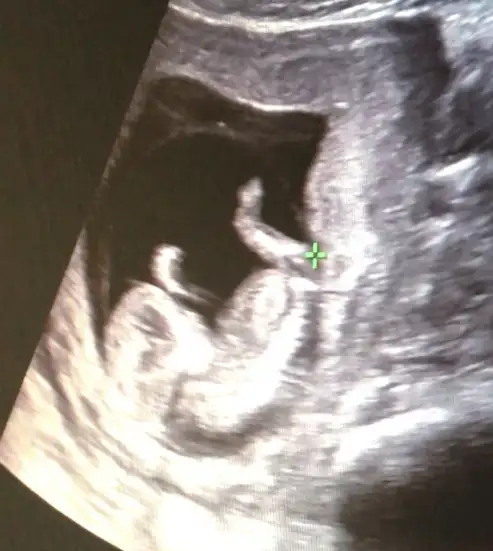

Bugün doktora gittik bizde ikili tarama için doktor bi tahmin de bulundu. Sizlerden de alayımmı tahmin kızlar fasulyemee:KK200::anneadayı: